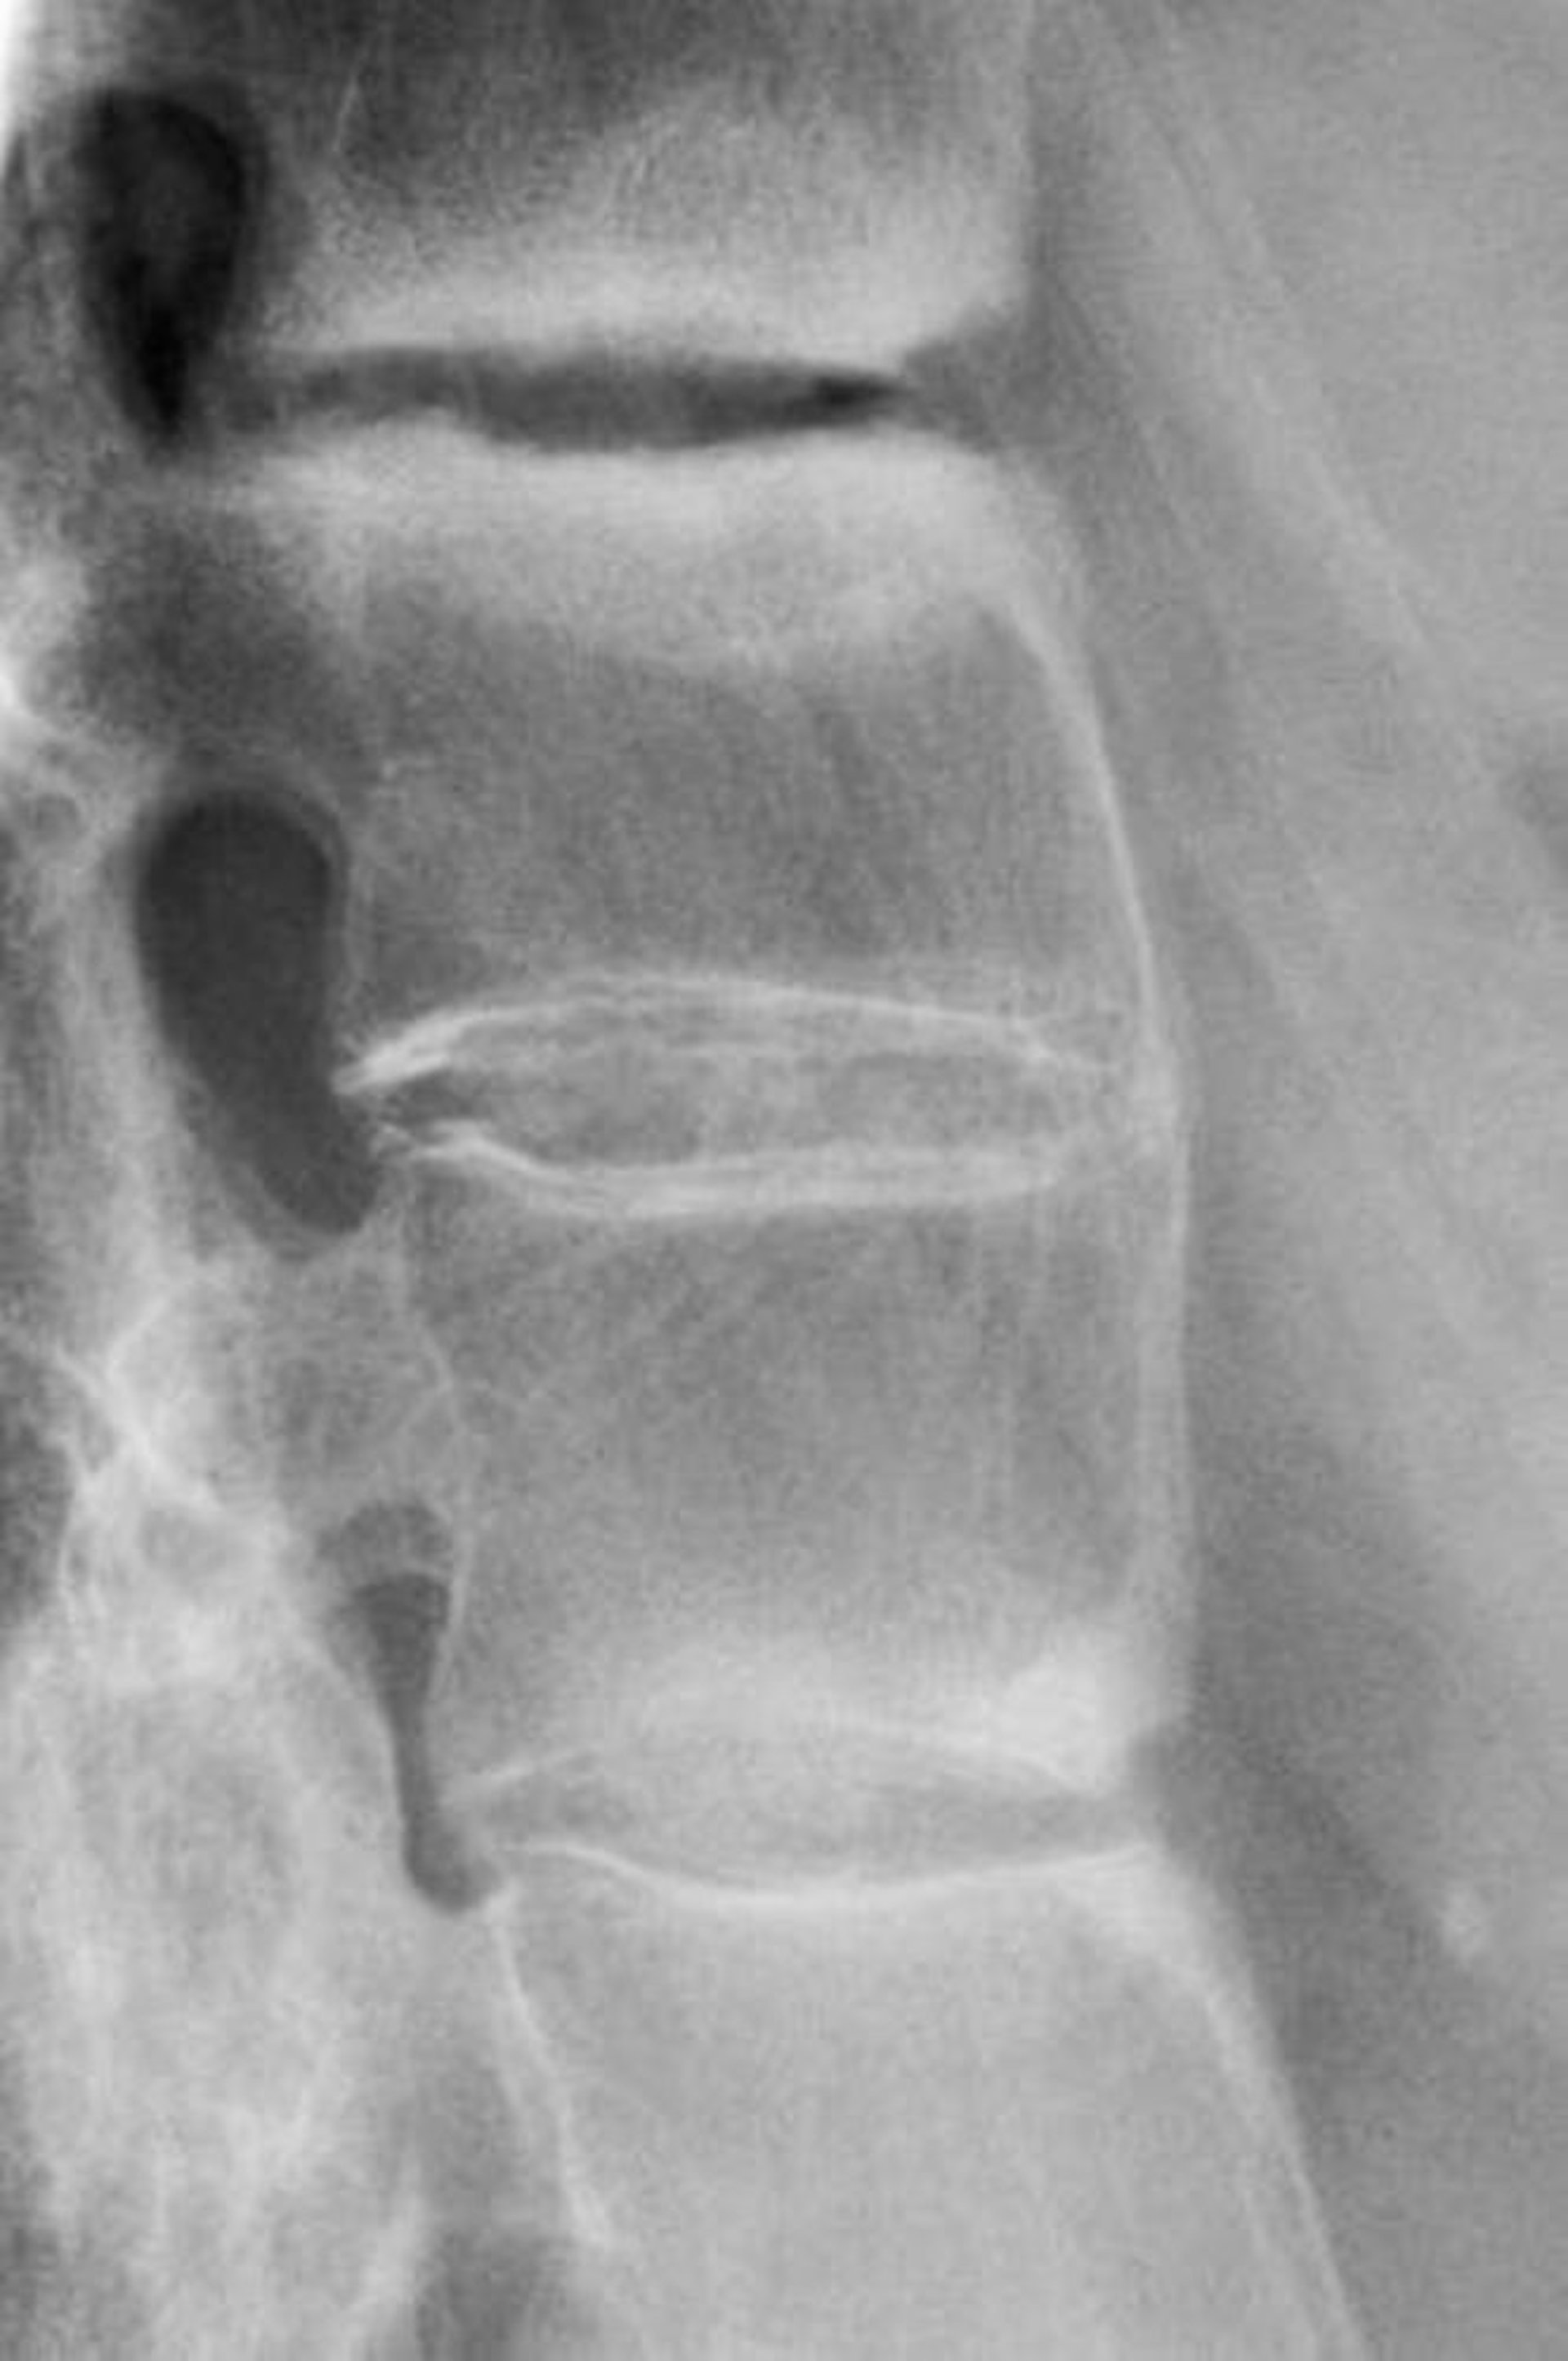

Spondylarthrite ankylosante

Cette radiographie montre une sclérose entre les vertèbres lombaires, une perte de la lordose et la fusion des vertèbres lombaires, un signe de spondylarthrite ankylosante avancée.

DR P. MARAZZI/SCIENCE PHOTO LIBRARY